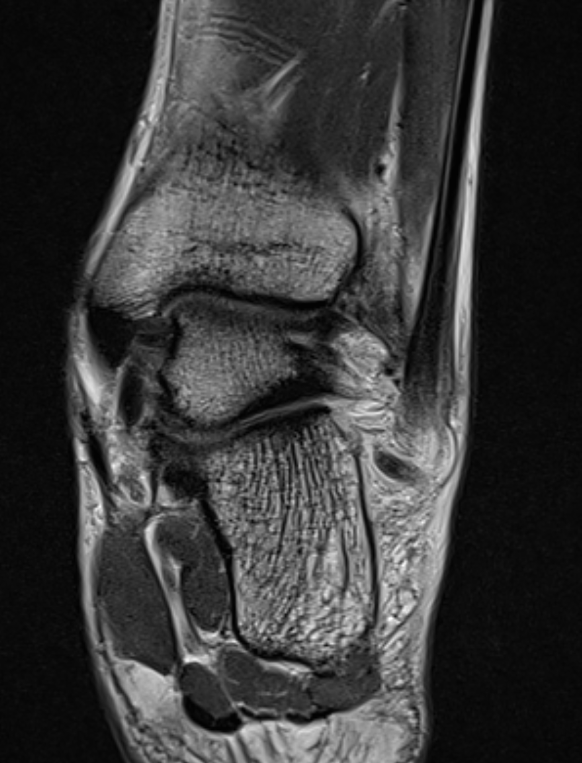

MRI

CFL tear